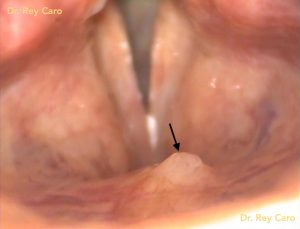

Caso: Granuloma de contacto de apófisis vocal derecha. Inyección de triamcinolona.

Granuloma de apófisis vocal. 30 días post inyecciónAblación de lesiones faríngeas y laríngeas con High Radiofrequency 4Mhz (Radiofrecuencia Controlada)

Caso 1: papiloma residual en cara superior de ambas cuerdas vocales

Foto: Papilomatosis de laringe: 30 días post extirpación de papilomas por vía oral bajo anestesia local